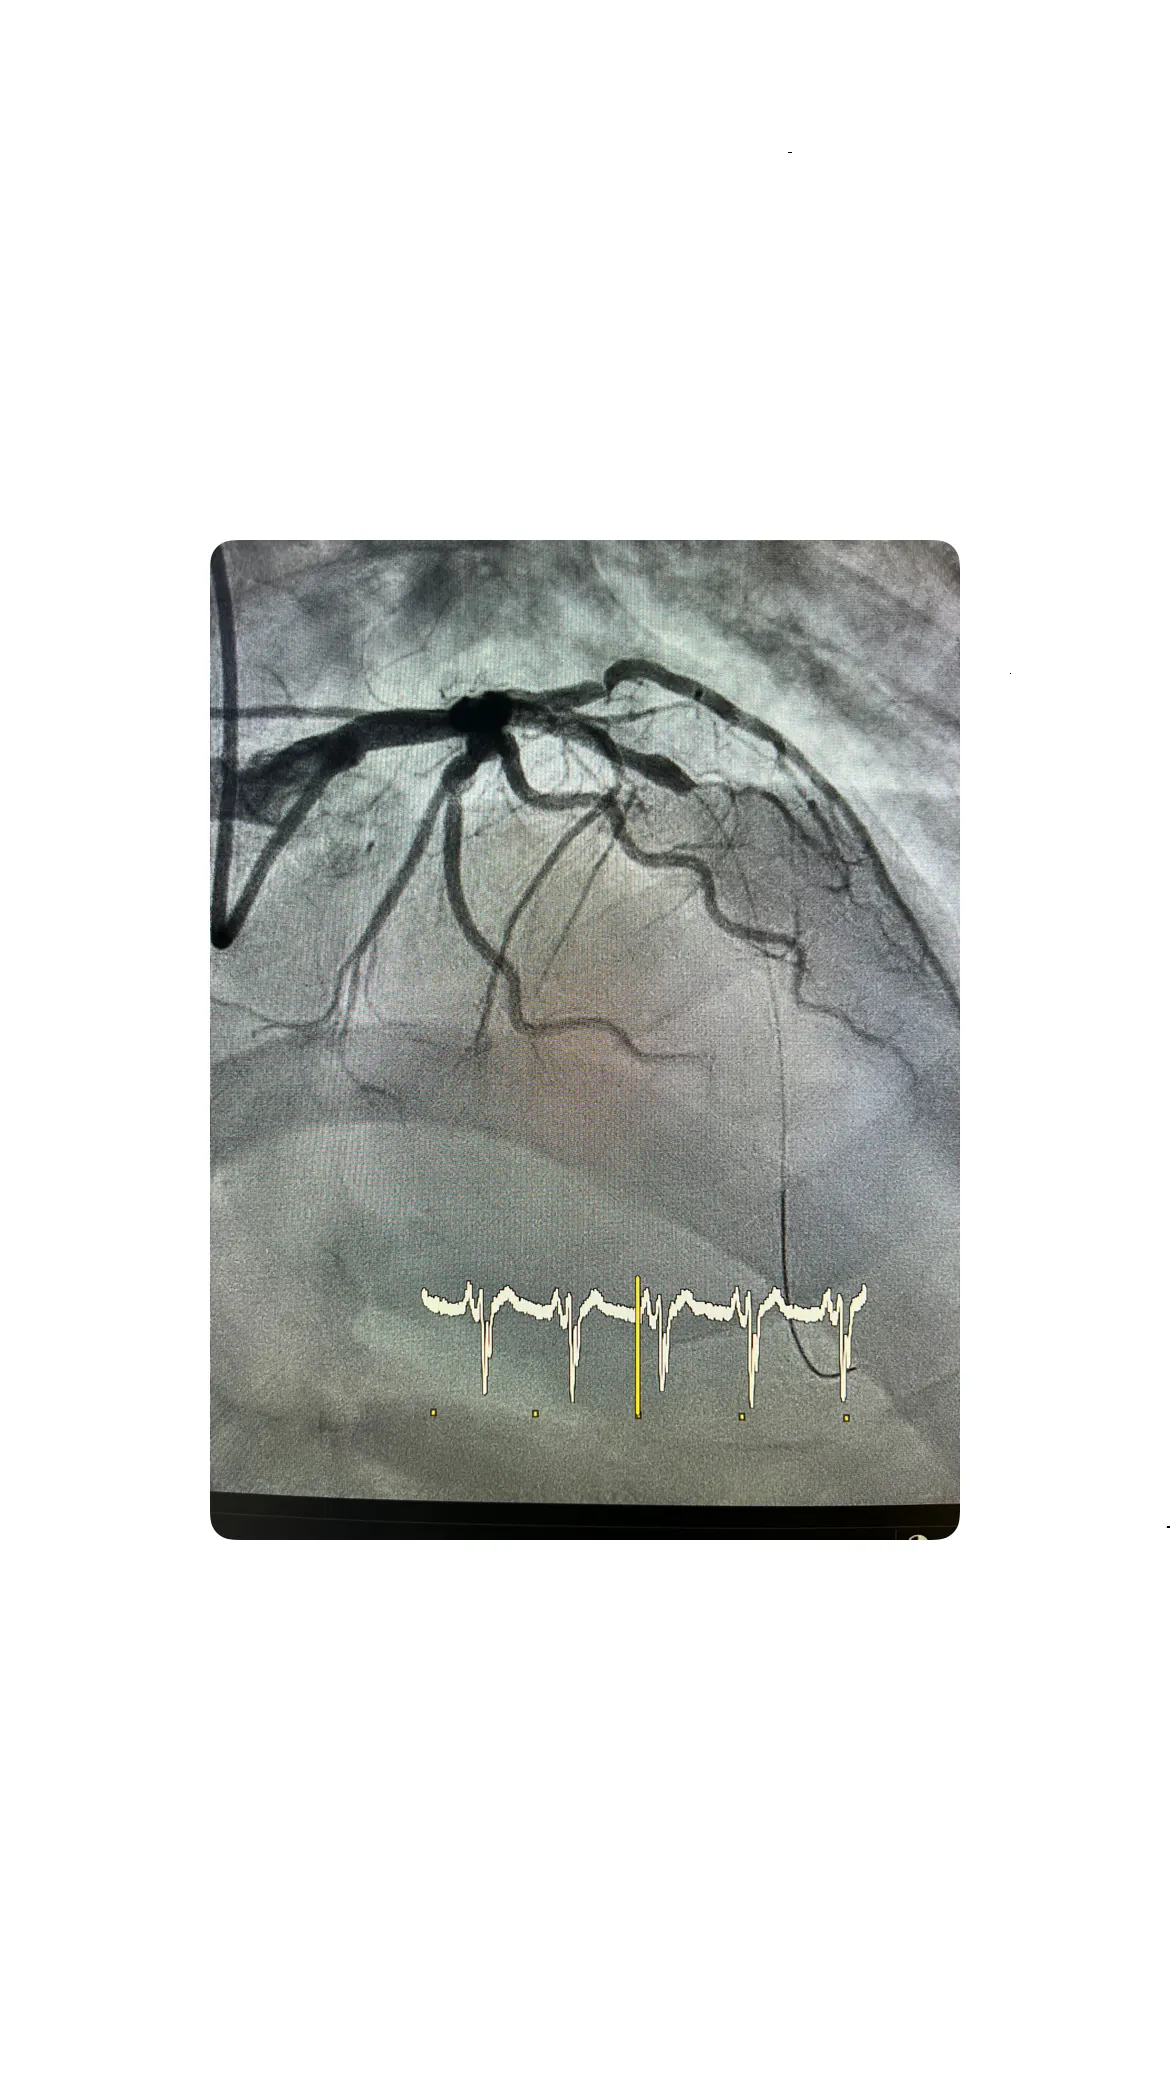

Implantación del stent y resolución de la lesión

Después de comprobar que la predilatación ha mejorado el paso de sangre, se decide implantar un stent en la zona de la lesión para asegurar que la arteria permanezca abierta de forma duradera. El stent se posiciona cuidadosamente en el segmento afectado de la descendente anterior y se expande hasta fijarse en la pared arterial. Una vez implantado, se vuelve a inyectar contraste para valorar el resultado final, observándose que la lesión queda resuelta y que el flujo coronario es adecuado. Esta resolución angiográfica se acompaña de una mejoría progresiva en el electrocardiograma, con tendencia a la normalización del segmento ST, lo que confirma que la reperfusión ha sido efectiva y que el objetivo principal del procedimiento se ha alcanzado.